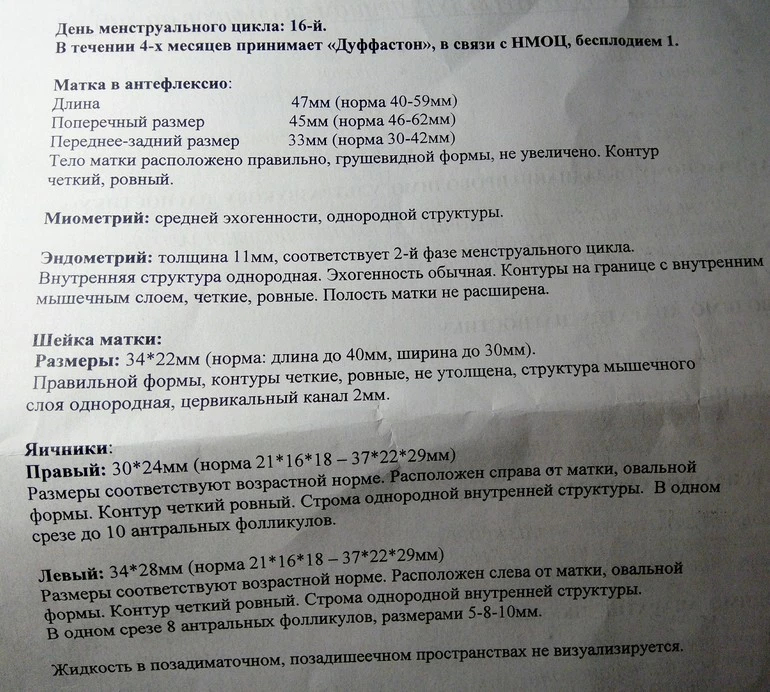

Мой результат УЗИ на 16 ДЦ Кто что может сказать? Тест на О положительный на 13 и 14 ДЦ.

Могли желтое тело не увидеть, а мог и сдуться фоликул, и не было овуляции. А то что эндометрий хороший - еще не показатель, у меня при здутии фолликула и при лютеинизации фолликула он тоже был отличный и соответствовал второй фазе.

в протоколе узи не слова о наличии доминантного фолликула, поэтому вряд ли была или будет овуляция в ближайшие дни

судя по узи овуляции не было,доминантного фолликула нет. хотя желтое тело может позже сформироваться